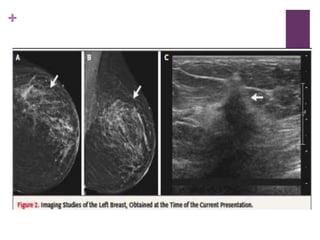

Mastografía + Tomosíntesis

 Mostraron en el cuadrante superior externo de la

mama izquierda que no había estado presente en la

mamografía previa y que se correspondía a la

anormalidad palpable; no se observaron masas,

calcificaciones o distorsión de la arquitectura en el

estudio de la mama derecha

Ultrasonido Mamario

 A las 2’ de la mama izquierda reveló una masa hipoecoica,

irregular, de 20x20x19 mm., localizada a 9 cms del pezón y

situado dentro de un reducto de tejido con textura

heterogénea que abarcaba la mayoría del cuadrante superior

externo.